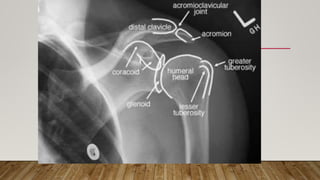

This document discusses radiology and the use of x-rays. It begins with an introduction to radiology and x-rays, noting their importance as the "father of medical investigations." It then discusses anatomy as seen on radiographs and whether x-rays are enough. The document goes on to compare gross views to radiological views, noting what each can and cannot show. It highlights important figures in the development of radiology, from x-rays to CT, MRI, and ultrasound. Specific anatomical structures visible on upper and lower limb x-rays are listed. The document concludes by discussing how pathologies appear on x-rays and the importance of clinical history and knowledge when interpreting radiological images.